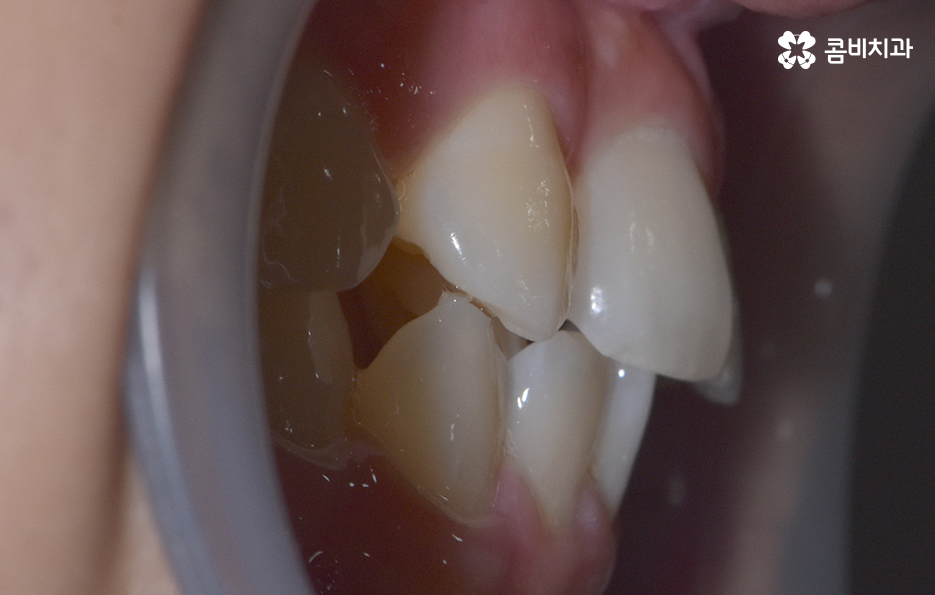

덧니가 나는 원인은 유전적인 영향부터 골격적인 부분 등 다양하지만 기본적으로는 치아가 나올 공간이 부족해서 덧니의 형태로 영구치가 자라는 경우가 많기 때문에 덧니 교정 사례에는 유독 발치 교정 사례가 많이 있는데요

다만 덧니 교정 사례에서 발치교정 사례가 많은 이유는 턱뼈가 좁아서 치아가 덧니로 자란 경우가 많기 때문에 치열을 재배열하기 위해서는 치아가 움직일 수 있는 충분한 이동공간이 필요하기 때문에 공간 확보의 목적으로서 작은 어금니 양옆, 위아래 4개를 발치를 하는 발치교정법이 보편적으로 많이 활용되고 있으며 치아의 이동 공간을 확보하는 방법으로는 발치 교정법 외에도 악궁확장, 어금니 후방이동, 치간삭제와 같은 비발치적인 방법도 가능하기 때문에 치아를 얼마나 이동시켜야 할지에 따라서 치료법은 개인차가 발생되고 있어요

발치교정이 필요한지 여부에 대한 판단은 치아의 이동 공간이 얼마나 필요하고 확보해야 하는지에 따라 달라지는데 이러한 판단 근거는 단지 치열만을 두고 보는 것이 아니라 골격과 얼굴형을 종합적으로 고려한다는 점에서 정밀검진과 함께 풍부한 경험을 갖춘 교정 전문의와 잘 상의하여 결정하신다고 보시면 될 거예요